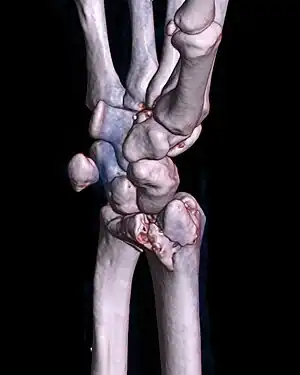

![]() | |

| A palmar Barton's fracture of the right wrist, as shown on a 3D-rendered CT scan | |